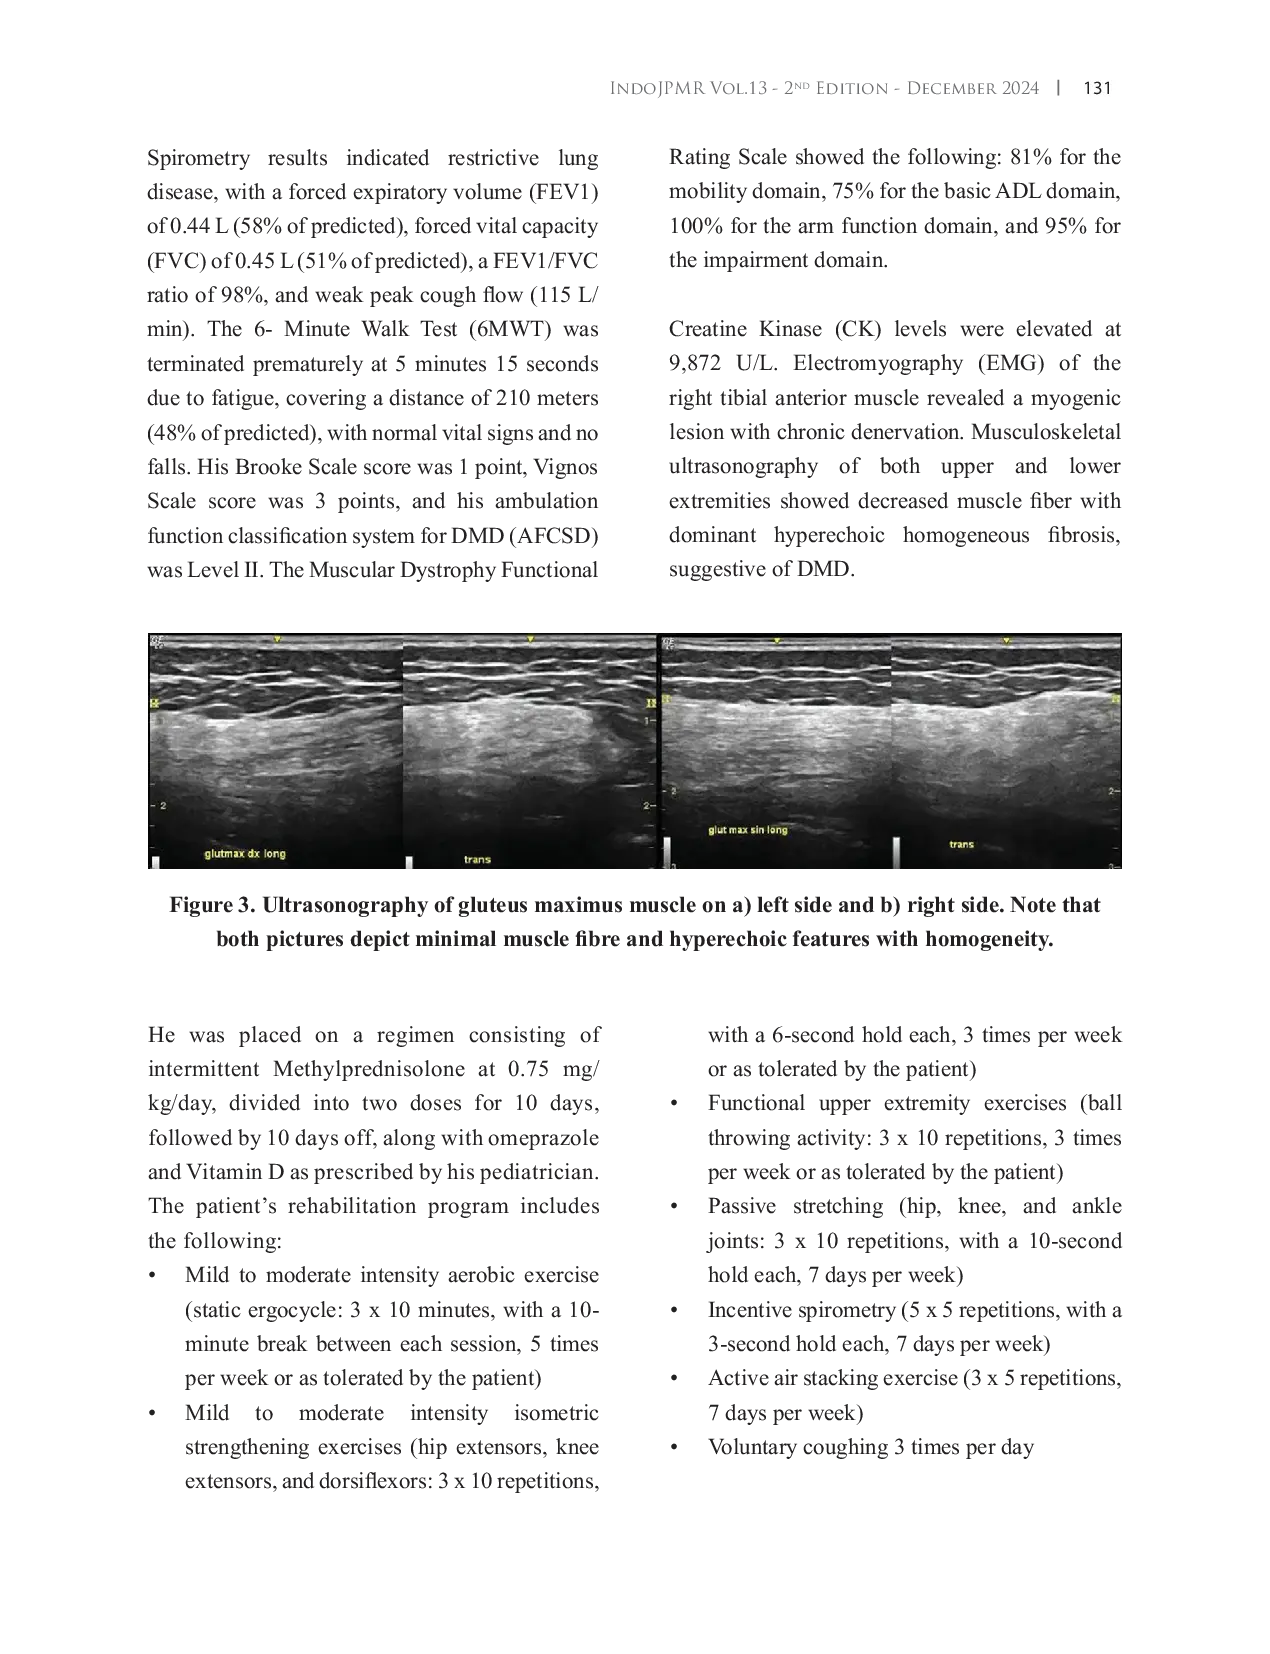

INDOJOURNALPMRINDOJOURNALPMR Evaluasi fungsi paru-paru dan manajemen sangat penting, mengingat hubungan komplikasi paru-paru dengan mortalitas pada DMD. Ergosiklus statis adalah pilihanEvaluasi fungsi paru-paru dan manajemen sangat penting, mengingat hubungan komplikasi paru-paru dengan mortalitas pada DMD. Ergosiklus statis adalah pilihan